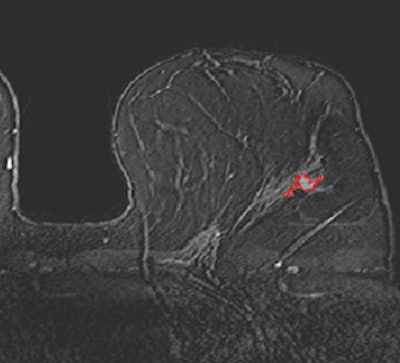

Breast DCE-MR images acquired on a 3-tesla scanner. Top, pure DCIS; below, invasive with DCIS; bottom, invasive cancer. Shown in these slices are the computer 3D lesion segmentation results. Images courtesy of Maryellen Giger, PhD.